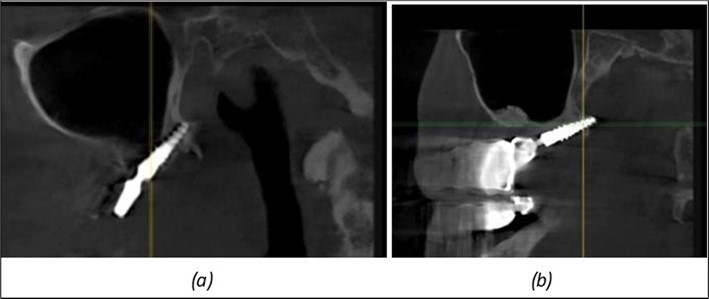

Figure 8.(a), (b) Sinus lift and grafting area with two stage implants before their removal. (c) area of fixation of BCS and TPG implants, avoiding the sinus lift and grafting area

Figure 9.Implants in the pterygoid plateau area: (a) TPG implant fixed in the maxillary-sphenoid junction area, quadrant 1; (b) TPG implant fixed in the maxillary-sphenoid junction area, quadrant 2.

Figure 10.Implants in the palatal sinus cortical area to avoid bone grafting: (a) BCS implant partially fixed in the graft material mass, partially in the palatal cortex; (b) Implant fixed in the palatal cortex at the junction with the nasal cortex, behind the graft material mass.